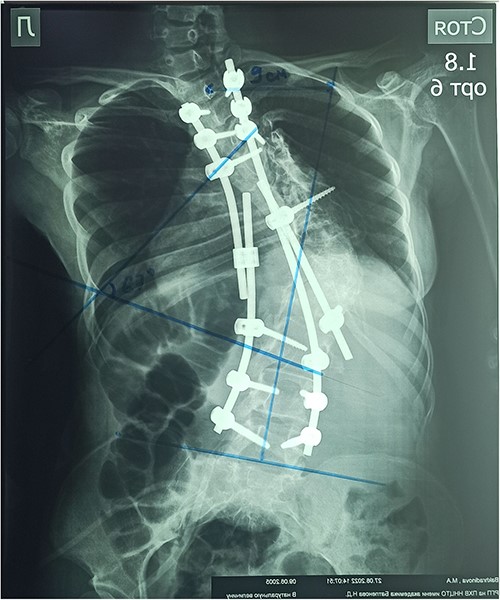

On the preoperative anterior–posterior X-ray, the Cobb angle was 110°; violation of frontal balance—13 cm (Fig. 2).

The patient underwent surgery: laminectomy of Th11, Th12, L1 vertebrae, partial excision of diastematomyelia, and decompression of the spinal cord; pedicular subtraction osteotomy at the level of Th9, Th10 vertebrae with resection of 11, and 12 ribs on the right side. Correction of congenital deformity and transpedicular stabilization (Medtronic, USA, no conflict interest) (Fig. 6).

In the early postoperative period, the patient complained of moderate local pain. There were no neurological disorders on the periphery of the lower extremities. The function of the pelvic organs was normal. On the seventh day after the operation, the patient underwent a X-ray control. After surgery, the Cobb angle was 67°, the correction was 60.9%, and the frontal balance was 9 cm (Fig. 7).